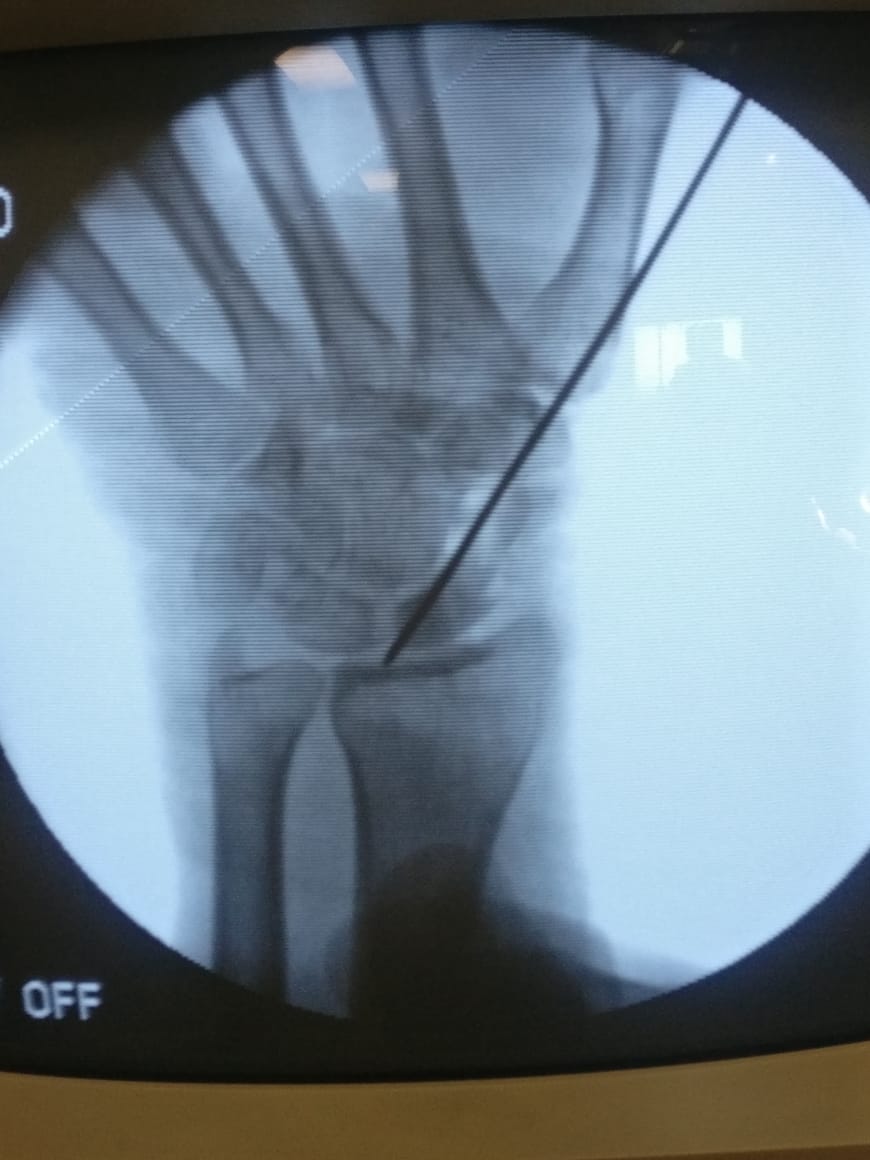

Fracture Scaphoid Treated With Bone Graft And k Wire Fixation